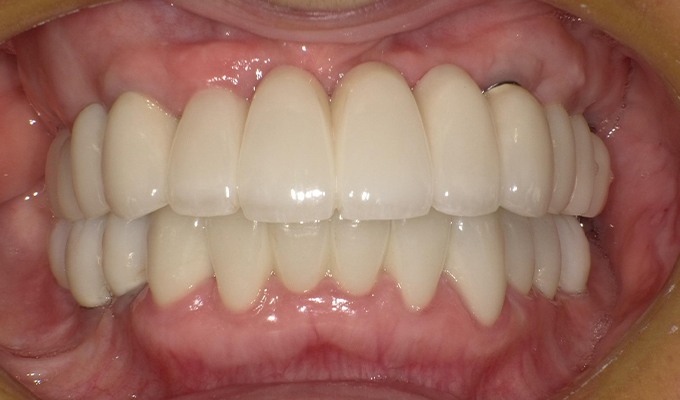

case5インプラント+メタルボンドブリッジ

初診時(2010年)

初回メンテナンス時(2012年)

最新メンテナンス時(2023年)

- 初診時の年齢

- 40代女性 (2010年)

- 主訴

- 5年ほど前に上に総入れ歯を作った。(マグネットタイプ)食事してたら人口歯が取れてしまった。インプラントに興味がある。40代なので入れ歯はやっぱり嫌、とのことでした。

- 治療内容

- 上・・・虫歯の根だけの歯が数本残っているためすべて抜歯し仮義歯作成しました。最終的には8本インプラントを埋入し上部構造はメタルボンドです。

下・・・保存できる下の歯はメタルボンドブリッジにし、奥歯のない部分に3本インプラントを埋入しました。治療期間は2年ほどかかりましたがしっかり食事ができるようになったので嬉しいと、満足していただけました。

以降定期的にメンテナンスに来院いただき11年経過してもいい状態を維持されています。